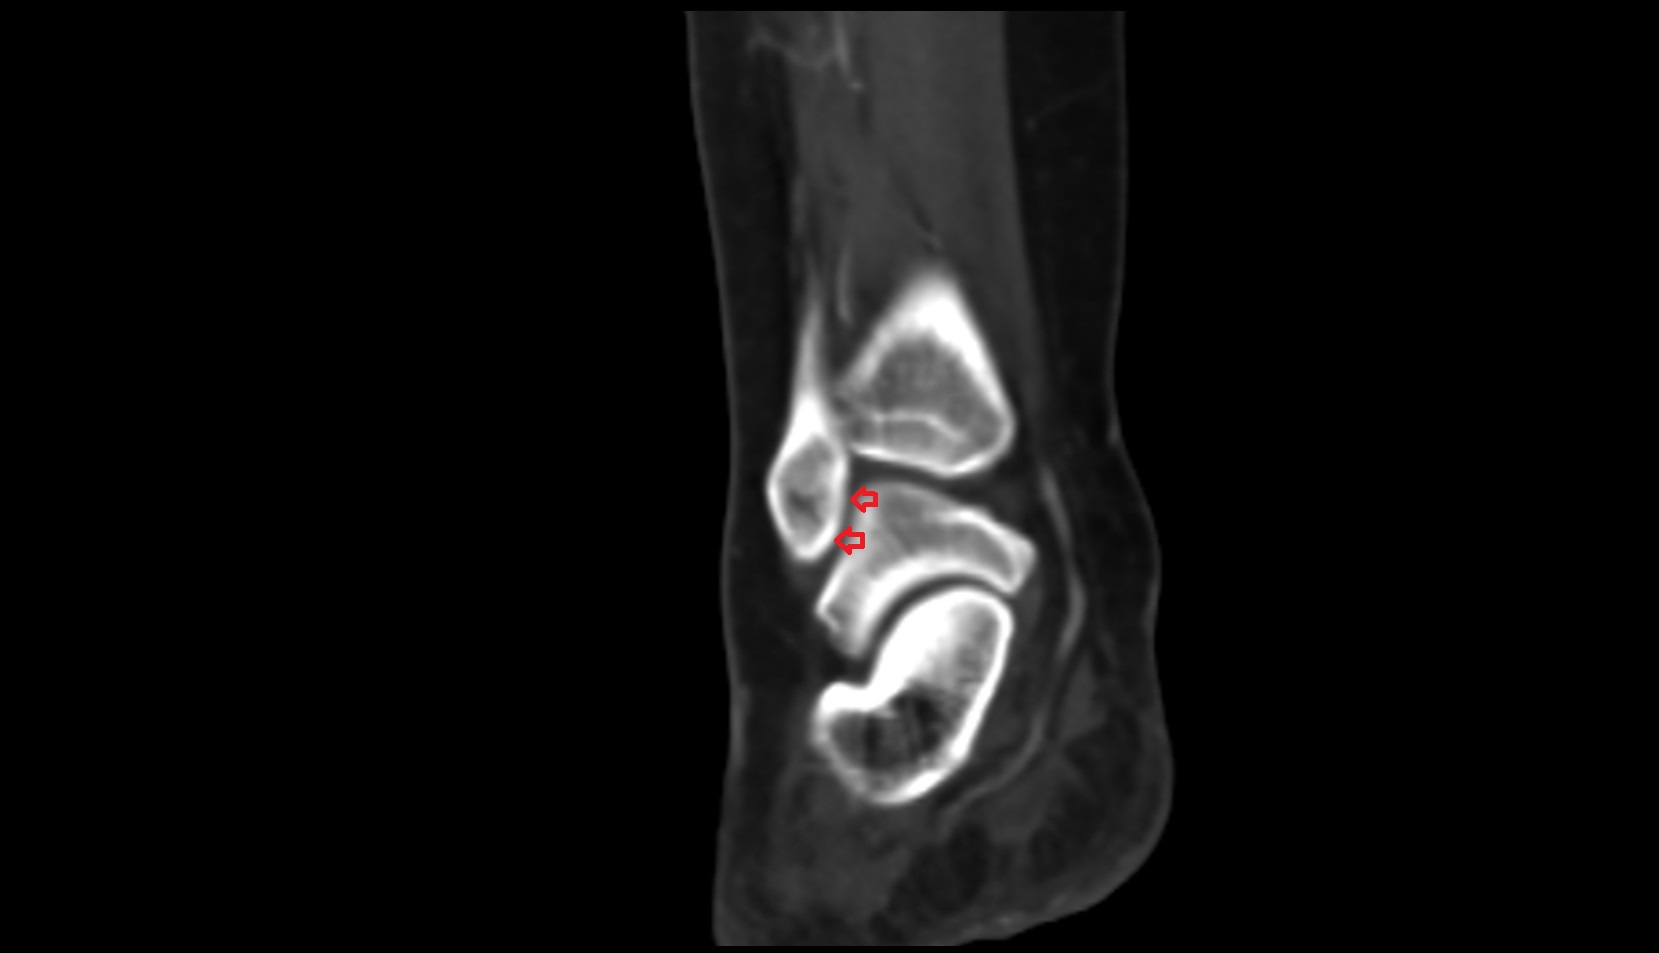

- Ankle joint

- Talus

- Calcaneus

- Anterior talofibular ligament

- Posterior talofibular ligament

- Deltoid ligament complex